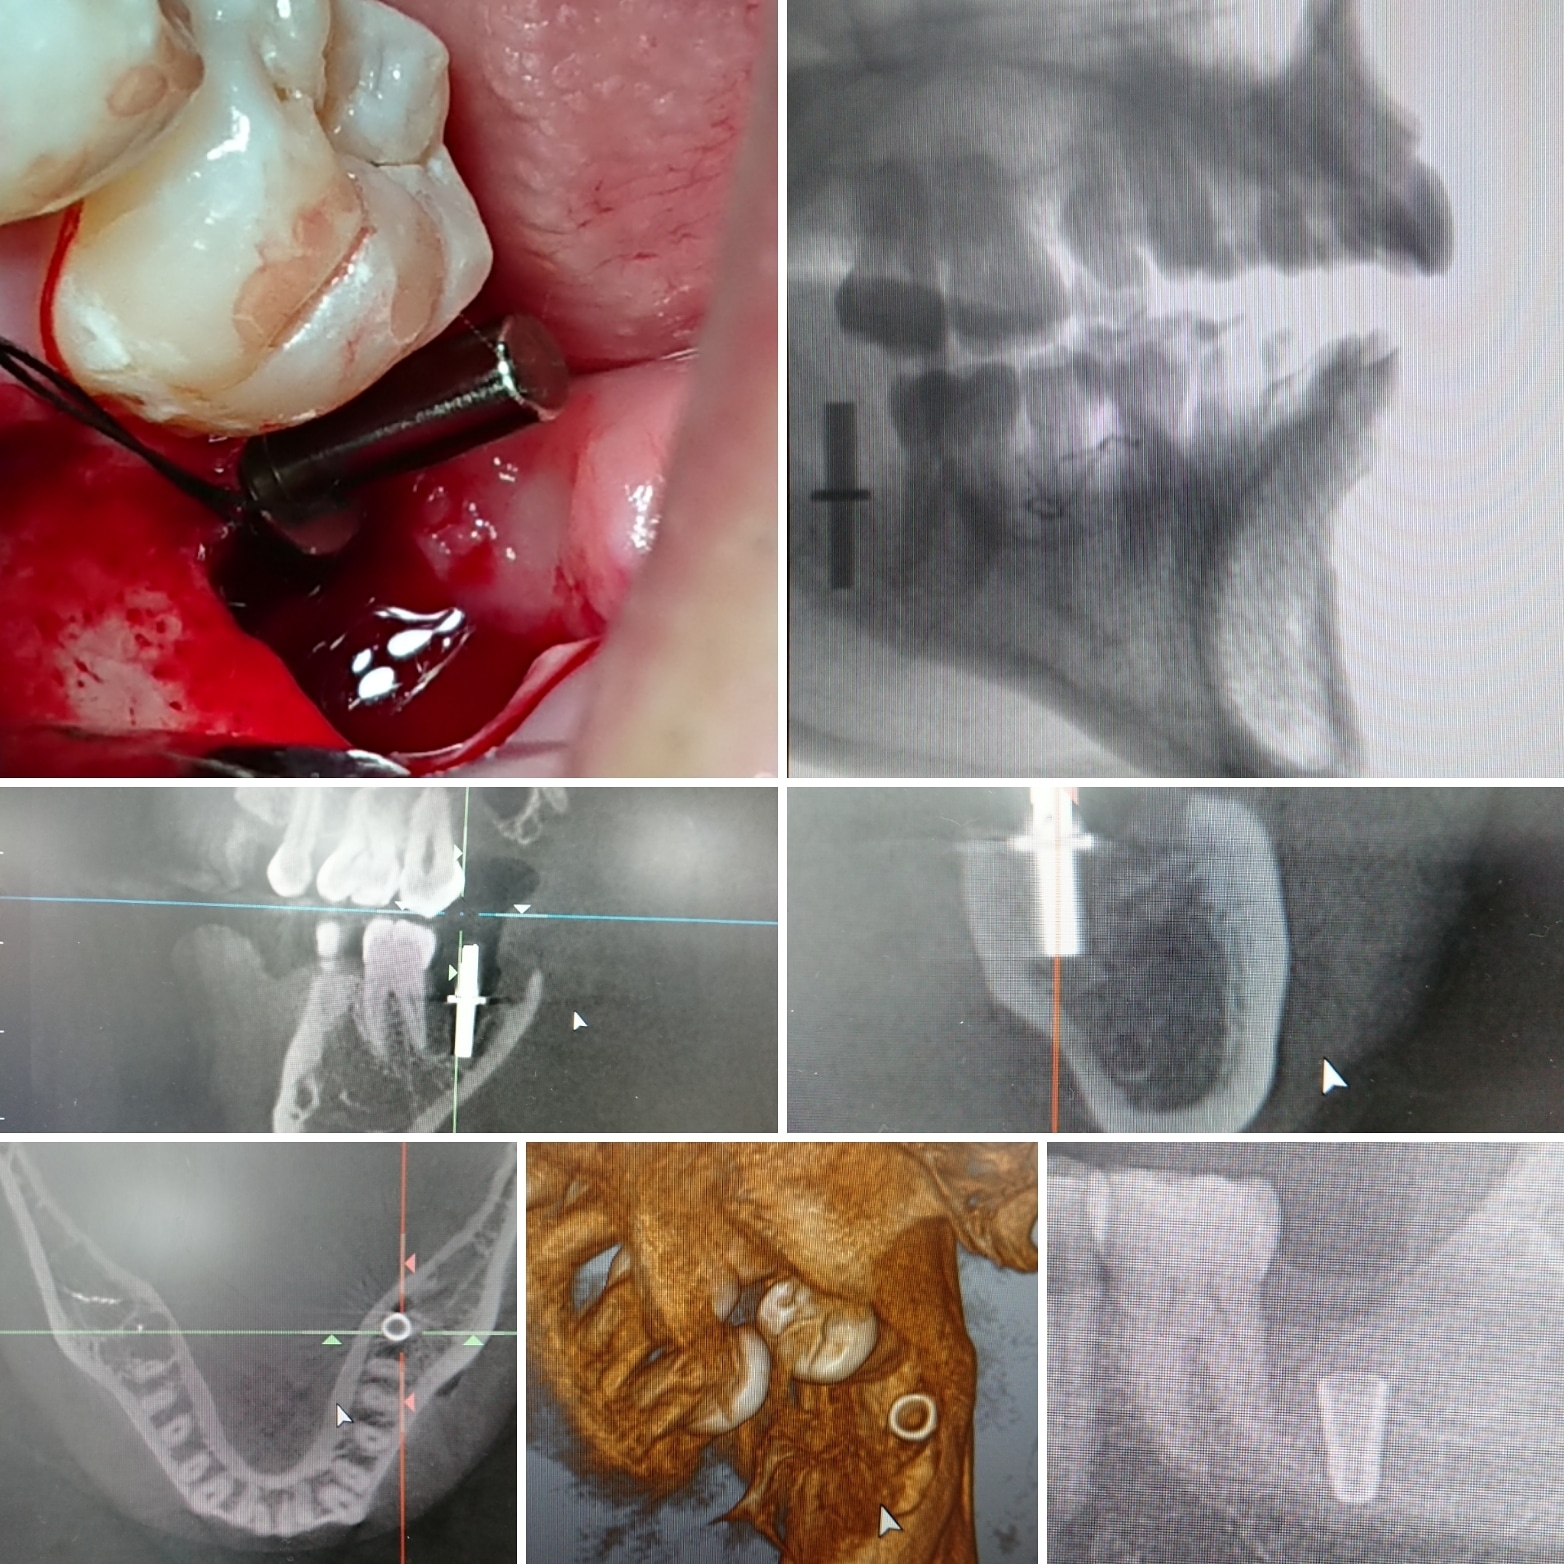

✳️左下奥7番、8番水平埋伏親知らずを抜歯した後、7番部にインプラント埋入

#ディレクションインジケータ

#埋入方向

#埋入深度

#確認

#口腔内写真

#CTスキャン画像